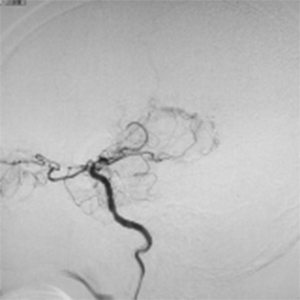

程度が軽い場合には、薬の治療(内科治療)のみを行います。程度が軽い方は、お薬だけで脳梗塞の再発を防げる場合も多いです。しかし、程度がひどい場合、脳血流が低下している場合には、お薬だけでは、2年で20%前後の人が脳梗塞の再発を起こすともいわれております。狭窄や閉塞は慢性的に詰まっており、再開通させることはできません。そのかわりに、頭皮の血管(主に、浅側頭動脈)を剥離し、頭の中の脳血管に顕微鏡を用い吻合することにより、脳の血流量を外から増やすバイパス手術を行います。浅側頭動脈中大脳動脈バイパス術(STAMCAバイパス術)といいます。バイパス術で脳の血流を増やすことにより、脳梗塞の再発する危険性を大きく減らすことできます。現在のガイドラインで推奨されている手術適応は、簡単にいうと73歳以下の比較的元気な方で、脳の血流が著しく低下している方です。最近は、平均寿命も延び、高齢な元気な方も増えております。国内、海外でも高齢者に対するバイパス手術で良好な成績を示す報告は増えております。当院でも、全身状態やほかのご病気の有無を確認し、全身状態が良い場合には、高齢者でも、十分な術前検査を行ったうえで、バイパス手術を行っており、良好な成績を出しております。

バイパス術で増加した脳血管

バイパス術により脳血流が正常化